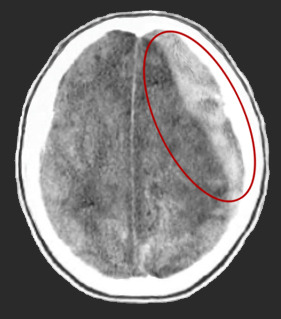

흔히 의식장애를 동반하며 반 혼수나 혼수상태에 빠질 수 있으며 경련성 발작을 일으킬 수도 있다. 뇌 전산화 단층촬영(CT)을 통하여 정확한 진단을 하게 된다.

뇌 전산화 단층촬영으로 급성 경막하 출혈을 진단하고 동시에 뇌 실질에 좌상(타박상), 열상(찢어짐), 뇌내출혈 등이 동반되어 있는지 확인할 수 있다. 또한 뇌 부종의 정도와 뇌가 압박을 받는 정도를 확인할 수 있으므로 환자의 상태를 이해하고 치료방침을 정하는데 매우 중요하다.

환자의 의식이 저하되고 있으며 전산화 단층촬영에서 출혈량이 상당하여 뇌가 압박을 받는 소견이 보인다면 수술적 치료가 필요하다. 일반적으로 두개골과 경막을 열고 응고된 혈괴(血塊)를 제거하여 뇌에 대한 압박을 풀어주는 수술을 하며, 심한 경우 혈괴를 제거하더라도 뇌 부종이 계속 진행되어 뇌압이 올라가는 경우가 많으므로 인조 경막을 써서 경막을 여유있게 봉합하고 그 위에 두개골을 닫지 않고 피부만 봉합하여 압력을 줄여주는 감압술을 하기도 한다.